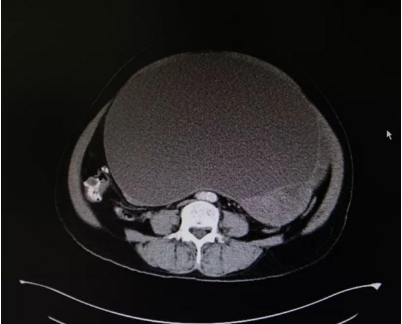

陈阿姨回忆,2018年8月自己刚刚出现腹胀时,由于没有腹痛、恶心、呕吐、便血、腹泻等不适,所以没有给予重视。随着日子一天天过去,到了今年2月份时周阿姨的肚子已隆起如“孕肚”一般,这时她才慌了神告诉了儿子。在厦门医院的检查显示,她的盆腹腔里有一个约271mm*178mm的巨大实性肿块,面对如此巨大的肿块,当地医院说陈阿姨心脏不好手术风险很大,让她先安装心脏起搏器才能手术。

在门诊初见陈阿姨时,王建南就判定她腹腔内有肿瘤包块,根据影像学检查结果,他判断该肿瘤以实性成分为主,“由于肿块巨大,占据了盆腹腔绝大部分空间,好在肿瘤有腹膜包着手术风险相对要小一点。”

王建南教授提到,陈阿姨的盆腹腔肿块来源于子宫底部,属于畸胎瘤,“肿瘤与子宫间有较致密黏连,幸运的是与腹腔及肠管无粘连,但肿瘤的体积大还是给手术增加了难度。”

上午九点,王建南教授团队小心翼翼开始为陈阿姨实施手术。在她的腹正中先切一长15cm切口,切开皮肤、皮下、腹直肌、腹膜,探查腹腔,可见一巨大肿瘤,包膜完整,沿原切口向上方延长切口至剑突下,可见肿瘤大小约20cm×20cm×20cm,形态较规则,肿瘤下方触及与子宫底粘连,用止血钳钳夹肿瘤根部,将肿瘤及部分子宫底完整切除,将肿瘤完好无损地搬离盆腔,将复杂的手术变得简单,最后利落干净地将部分子宫底完整切除。术中出血仅30ml,在场医护人员都赞叹不已。切除的肿瘤标本重达15多斤,用7号线缝扎残端,再次探查腹腔未见明显出血,留置盆腔引流管一根,逐层关腹。